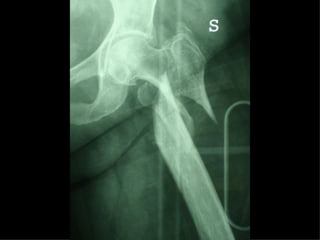

La placca a compressione percutanea (PC.C.P.) di Gotfried è un mezzo di sintesi studiato per assicurare un “impattamento controllato” delle fratture pertrocanteriche grazie alle due viti telescopiche prossimali che garantiscono una ottima stabilità rotazionale

Tradizionalmente si ritiene importante per la stabilità delle fratture pertrocanteriche l’integrità della parte mediale della metafisi prossimale del femore

In realtà la zona più importante per la ricostruzione di questo tipo di fratture è il muro laterale contro il quale si impatta il frammento metaepifisario mediale

Se il muro laterale è rotto o viene lesionato durante la sintesi , come spesso accade in fase di applicazione della vite cefalica dei chiodi endomidollari o della vite-placca, andremo incontro al collasso della frattura e ad un conseguente lungo periodo di impotenza funzionale

Con la placca di Gotfried non si è mai riscontrato un danno iatrogeno del muro laterale e nessun collasso della frattura.Ciò è dovuto al fatto che i fori per l’applicazione delle due viti prossimali sono di piccolo diametro (9 mm) rispetto ai 16-32 mm necessari per introdurre la vite cefalica di un chiodo endomidollare o di una vite-placca a compressione.